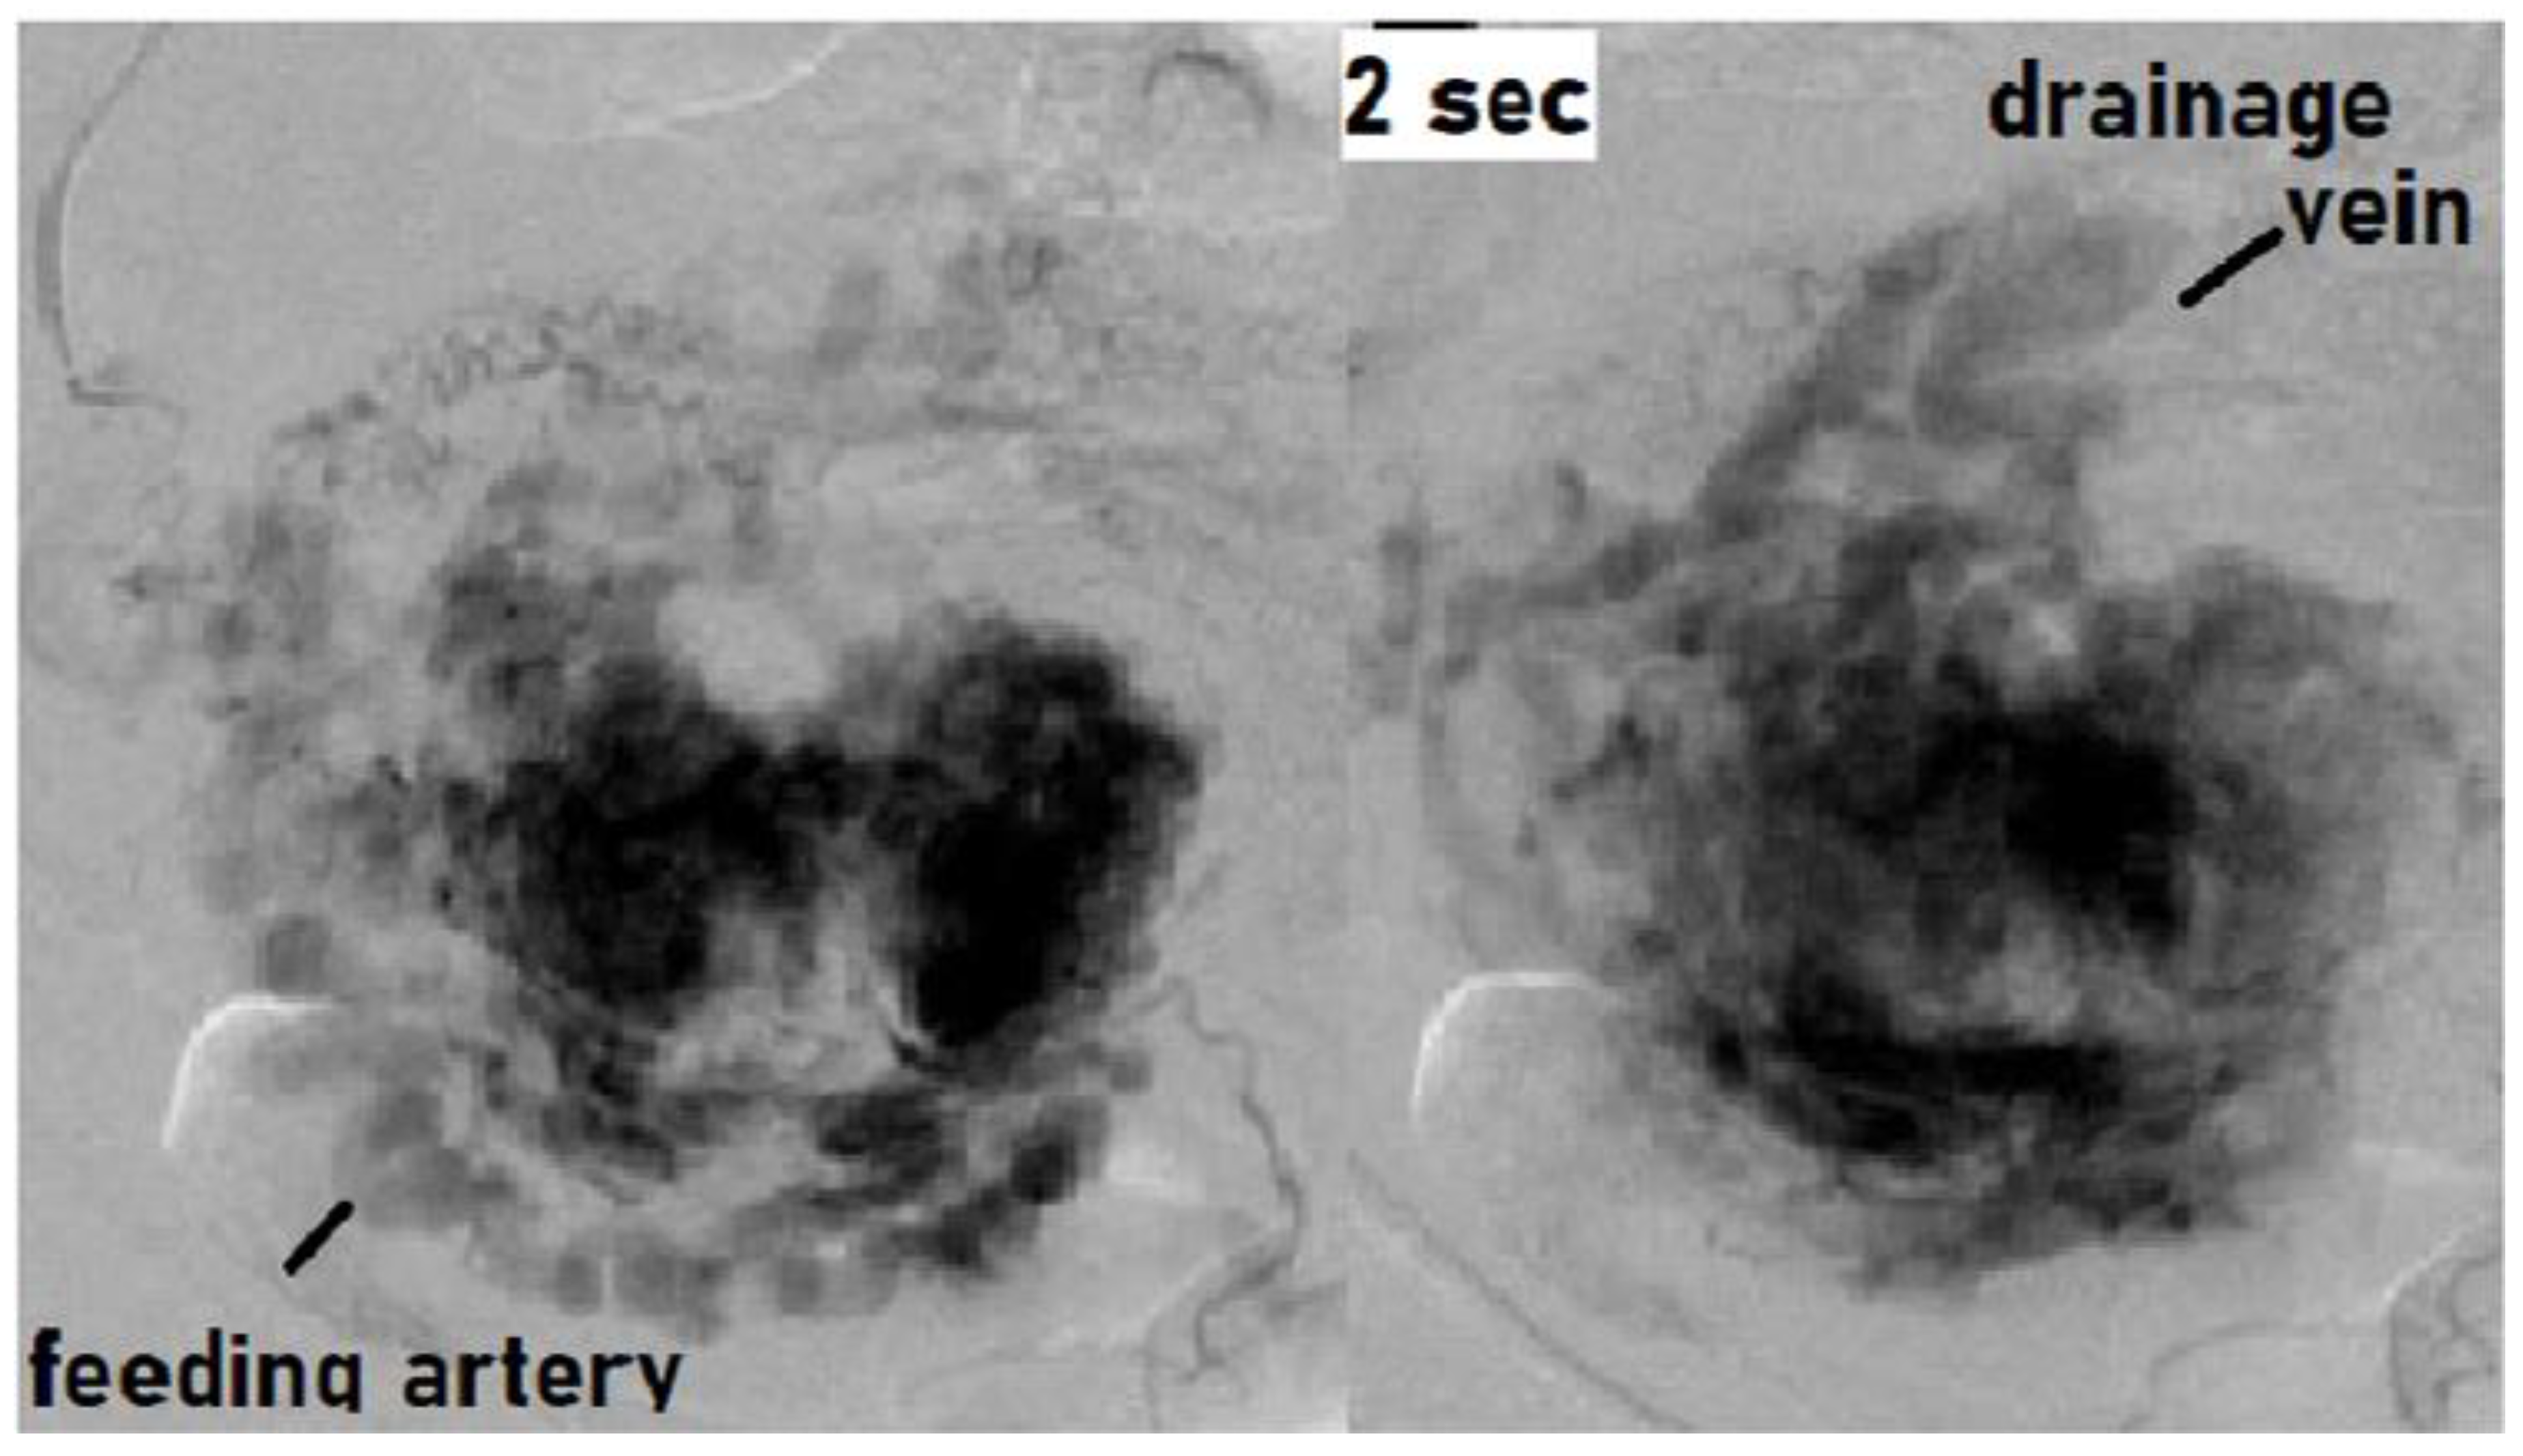

We treated a patient with suspected RPOC with vascularization that was, in fact, an AVM. We describe this case below. This case involved a 28-year-old, gravida 1 para 0 woman whose pregnancy progressed without any particular complications. On day 281 of pregnancy, the spontaneous delivery of a 3175-g girl occurred. The placenta was expelled and showed no apparent signs of a defect 13 min postpartum. Massive bleeding occurred suddenly 2 h postpartum, with blood loss since delivery totaling 1271 g. The administration of a uterotonic in combination with intravaginal gauze packing successfully stopped the bleeding. Transabdominal ultrasonography showed an intrauterine mass measuring 45 × 35 mm2, raising suspicion of RPOC. Ultrasound showed a hypervascular appearance with turbulent flow on color Doppler, and this was initially thought to be typical RPOC with vascularization. On close observation, however, the hypervascularity was limited to the point of contact between the remnant and the myometrium, and there was no pulsatile perfusion in the remnant itself (Figure 1) [19,21].

Figure 1. Findings of color Doppler ultrasound: Hypervascular appearance with turbulent flow. The hypervascularity was limited to the point of contact between the remnant and the myometrium, and there was no pulsatile perfusion in the remnant itself.